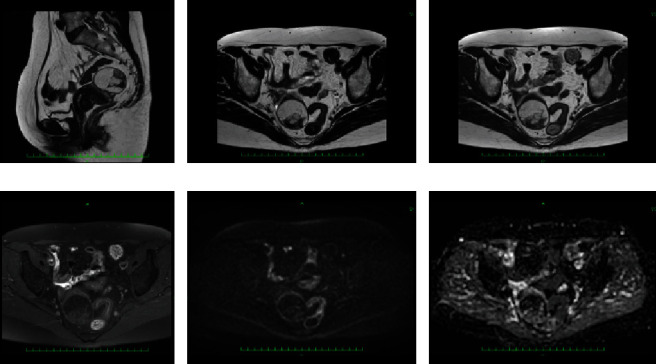

本研究报告了一例子宫脂肪肉瘤病例,并对相关文献进行了综述。患者 52 岁,经核磁共振检查确诊为脂肪组织肌瘤。患者的子宫体前壁有一个突出的肿块(39 × 32 × 41 mm3)。患者 58 岁时,她之前的医生发现肿瘤长大了,于是将她转诊到我院妇科。核磁共振成像显示,与之前的成像结果相比,肿瘤的大直径长了 1.23 倍,体积增大了 1.85 倍。弥散加权成像未发现明显异常信号。因此,恶性肿瘤被纳入鉴别诊断。患者同意接受全腹子宫切除术和双侧输卵管切除术。前壁的肿块完全留在子宫肌层中。腹腔内未发现种植,也未发现腹水。切口表面未发现出血或坏死。从组织病理学角度看,脂肪细胞和基质细胞的大小存在差异。细胞核结果不规则。免疫组化结果如下:CDK4(+)、desmin(+)、S100p(-)和 Ki - 67 = 1%。因此,诊断结果为分化良好的脂肪肉瘤。病灶位于子宫内,手术中将其完全切除。子宫原发的分化良好的脂肪肉瘤在完全切除后没有复发的可能,因此,患者接受了后续治疗,没有接受额外的治疗。术后 10 个月未发现转移或复发。

This study reports a case of uterine liposarcoma together with a literature review. At 52 years old, our patient was diagnosed with lipoleiomyoma by MRI. A mass (39 × 32 × 41 mm3) protruding from the anterior wall of the uterine body was observed. When the patient was 58, her previous doctor found that the tumor had grown, and she was referred to the gynecology department of our hospital. On MRI, the major diameter was 1.23-fold longer and the volume was 1.85-fold higher compared with the prior imaging findings. Diffusion-weighted images revealed no significant anomalous signals. Thus, malignant tumors were included in the differential diagnosis. The patient consented to total abdominal hysterectomy and bilateral salpingo-oophorectomy. The mass on the anterior wall remained completely in the myometrium. No implantation was found in the abdominal cavity, and ascites was not detected. No bleeding or necrosis was observed on the cut surface. Histopathologically, differences in the sizes of adipocytes and stromal cells were identified. There were irregularities in the nuclear findings. The immunohistochemical findings were as follows: CDK4 (+), desmin (+), S100p (-), and Ki - 67 = 1%. Therefore, a diagnosis of well-differentiated liposarcoma was rendered. The lesion was localized in the uterus, and it was completely removed during surgery. Well-differentiated liposarcoma of uterine primary has no possibility of recurrence following complete resection, and thus, the patient underwent follow-up without additional treatment. No metastasis or recurrence has been observed for 10 months after surgery.